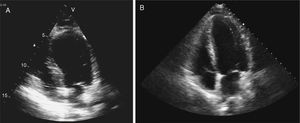

Case reportA 56-year-old Caucasian patient with COPD (irregularly treated with tiotropium bromide, acetylcysteine and mometasone) was admitted to the emergency room (ER) of our hospital with dyspnea and cough with sputum for two weeks. On admission to the ER, the patient was hemodynamically stable (systolic/diastolic blood pressure: 126/65 mmHg; heart rate: 98 bpm), eupneic at rest and with fever (39.1°C). Pulmonary auscultation revealed rumbles in the left hemithorax. The chest radiograph showed left paratracheal consolidation. There was no evidence of respiratory failure on arterial blood gas analysis. Laboratory tests revealed elevated leukocytes. After treatment with inhaled ipratropium bromide, the patient suffered severe bronchospasm and retrosternal chest pain accompanied by sweating and pallor. An electrocardiogram (Figure 1A), with pain, showed sinus tachycardia (heart rate 110 bpm), incomplete right bundle branch block, 2-mm ST-segment elevation in leads V1–V3 and Q waves in leads V3–V6. Given the possibility of an acute coronary syndrome, emergency coronary angiography was carried out, which showed normal coronary arteries (Figure 2A and B), severe systolic dysfunction with mid-apical akinesia and basal hypercontraction (Figure 2C). The echocardiogram confirmed severe compromise of left ventricular systolic function (LVSF), with akinesia of the mid-apical segments and an aneurysm-like dilatation (Figure 3). During hospitalization the patient remained hemodynamically and electrically stable, but the electrocardiographic pattern evolved with T-wave inversion in the left anterior precordial leads (Figure 1B) and plasma troponin I was elevated (peak value 2.28 ng/ml). After further use of ipratropium bromide, on the second day of hospitalization, the patient developed a new episode of marked bronchospasm and respiratory acidosis (pH 7.29; pCO2 53 mmol/l). He was started on non-invasive ventilation and was treated with hydrocortisone, inhaled salbutamol and furosemide, with progressive clinical improvement. He was also started on antibiotics (azithromycin plus ceftriaxone), but microbiological screening (bacteriological study of sputum and search for urinary antigens of Streptococcus pneumoniae and Legionella pneumophila) was negative. There was no significant increase in C-reactive protein levels. Repeat chest radiograph documented pulmonary overinflation. To assess the severity of lung disease, respiratory function tests were performed, which revealed a severe obstructive ventilatory syndrome with lung hyperinflation. The patient underwent a chest computed tomography scan on the fifth day after admission that showed scattered bronchiectasis and a ground-glass pattern in the area of the left lower lobe bronchus. The setting was interpreted as an infection in the process of resolution. Echocardiographic reassessment (Figure 3B) on the sixth day of hospitalization showed recovery of LVSF, with no segmental wall motion abnormalities, which was confirmed by cardiac magnetic resonance imaging (LVEF 57%) with no areas of delayed enhancement (Figure 4). The patient was discharged seven days after admission, treated with lisinopril 2.5 mg/day and inhaled salmeterol/fluticasone propionate. At six months of follow-up, no events had been registered.

Transthoracic echocardiogram in 4-chamber apical view (systolic frames) on admission revealing akinesia of the mid-apical segments and aneurysmatic dilatation (A) and echocardiographic reassessment (B), on the sixth day of hospitalization, showing recovery of left ventricular systolic function, with no segmental wall motion abnormalities.